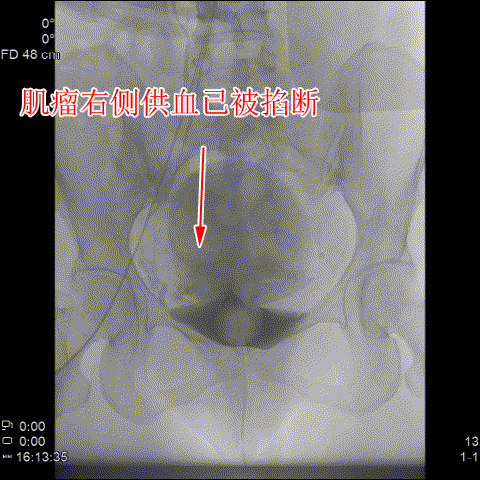

△術後造影可見肌瘤左右側的供血已被掐斷。

随後,李旭丹主任與胡志華主任聯手爲患者實施手術,通過患者股動脈穿刺,置入微導絲、導管,經動脈自然腔道将導管送達左右側髂總動脈進行造影,可見肌瘤供血血管,随後利用微導管将特制栓塞材料送達子宮動脈進行栓塞。造影顯示子宮肌瘤供血已被掐斷,順利完成手術。